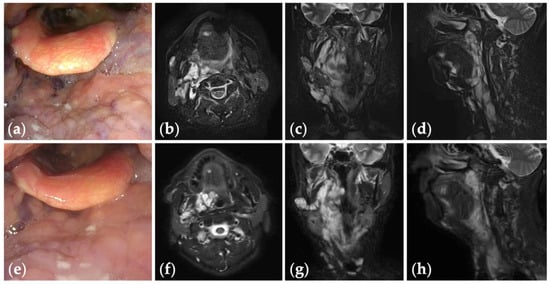

Figure 4.

Patient 10 graded “excellent” for treatment outcomes after three sessions of fluoroscopy- and endoscopy-guided transoral sclerotherapy: (a) an initial endoscopic photograph of the epiglottis of a 43-year-old man with pharyngeal venous malformation, and (e) the latest endoscopic photograph six months after the final sclerotherapy session at the age of 45 years; (b–d) short tau inversion recovery T2-weighted magnetic resonance images before treatment, and (f–h) three years after the final sclerotherapy session at the age of 47 years.